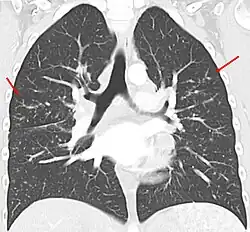

Sarkoidose in der Computertomographie koronar: Stadium II mit vielen kleinen Granulomen in der Lunge auf beiden Seiten (Pfeile). Die vergrößerten Lymphknoten an den Hili und im Mediastinum sind im Lungenfenster nicht so gut zu erkennen.